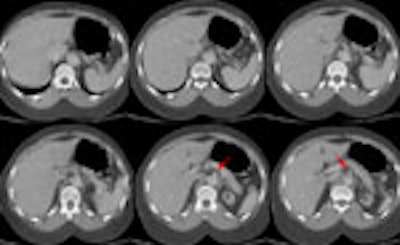

Images from the abdomen revealed the dissection extending into the superior

mesenteric artery with severe compromise of the native lumen (red arrow).